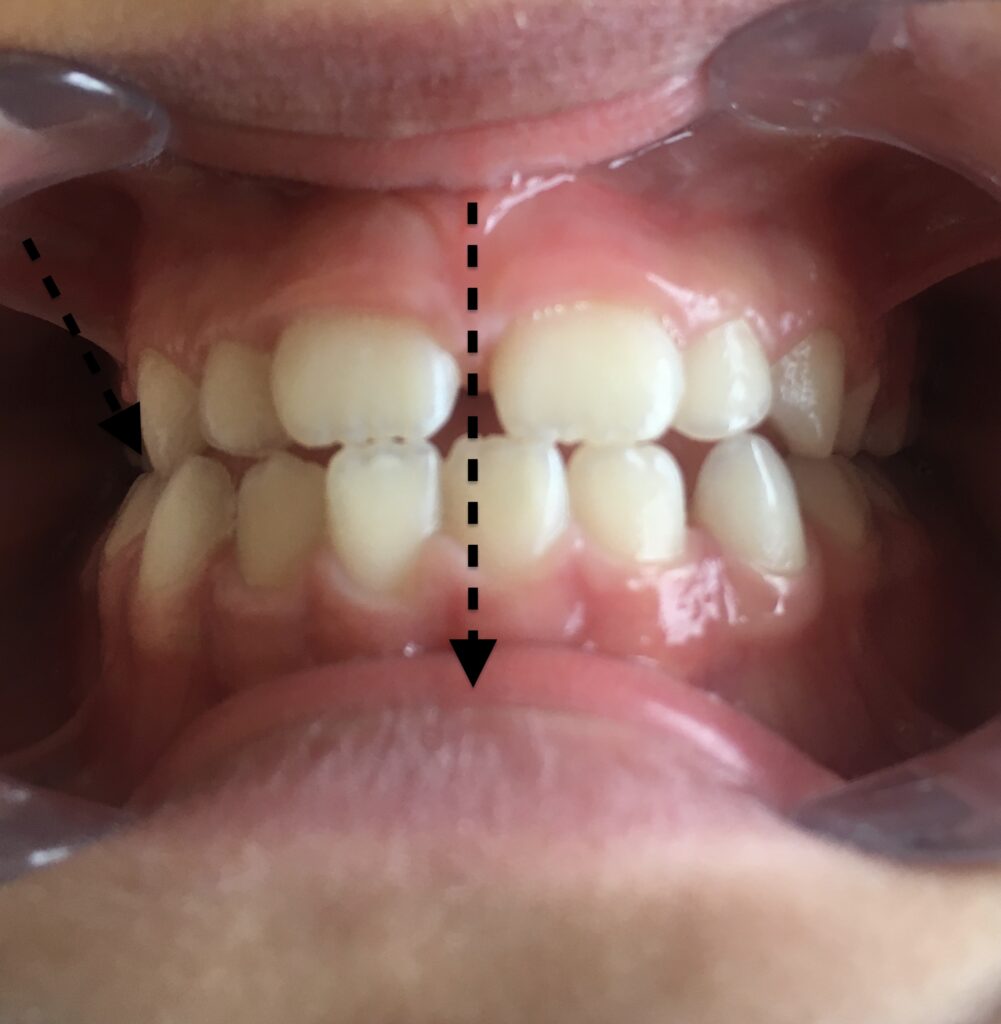

📸 Parfois, une image vaut mieux qu’un long discours…

Voir les photos avant/après sur Instagram : Instagram